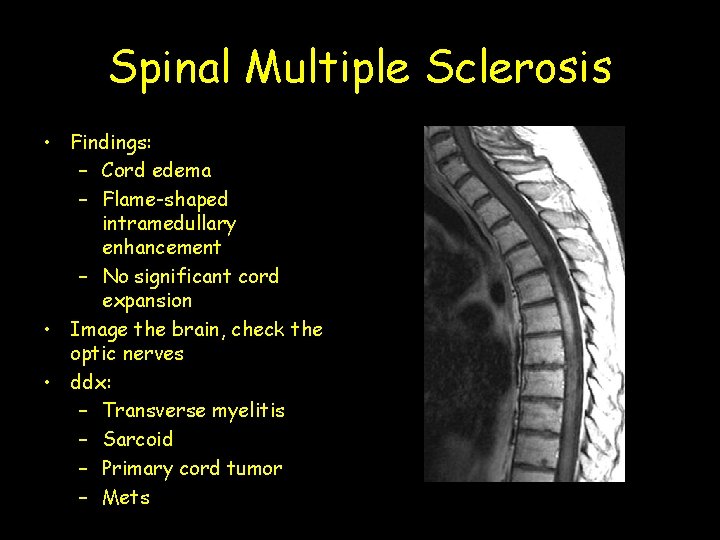

Spinal Multiple Sclerosis • Findings: – Cord edema – Flame-shaped intramedullary enhancement – No significant cord expansion • Image the brain, check the optic nerves • ddx: – Transverse myelitis – Sarcoid – Primary cord tumor – Mets